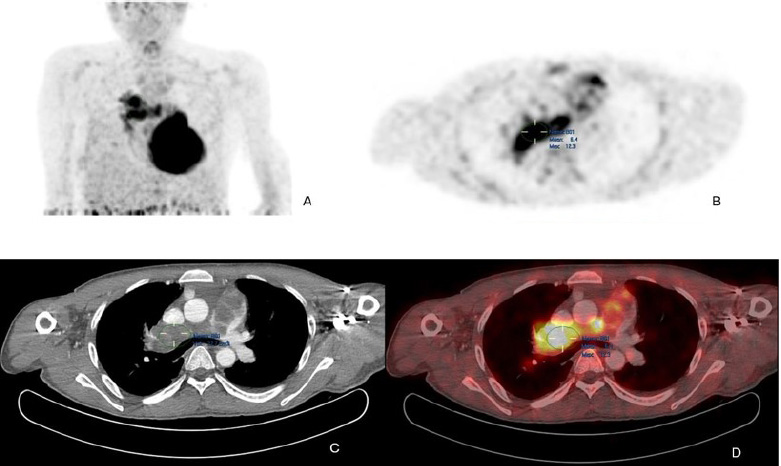

The patient was further investigated with computed tomography (CT), cardiac magnetic resonance imaging (MRI), and positron emission tomography-computed tomography (PET-CT). The CT scan showed a mass extending from the RVOT into the main pulmonary trunk, causing significant stenosis. PET/CT showed a fluorodeoxyglucose (FDG) avid lesion in the right ventricular outflow tract region extending to the right main pulmonary artery and the lobar arteries (Fig. 2A-D). Cardiac MRI showed an enhancing filling defect within the RVOT, main, and right pulmonary arteries, suggestive of a neoplastic process, most probably a pulmonary artery angiosarcoma. Signs of right heart volume and pressure overload were also seen (Fig. 3A-D). The patient also had a right-sided pleural effusion.

(A) Maximum intensity projection (MIP) FDG PET/CT of the thorax demonstrates heterogeneous FDG avidity overlying a branching linear structure in the right side of the mediastinum.

(B) Axial PET image shows an intensely FDG-avid linear lesion in the superior right mediastinum, with a maximum standardized uptake value (SUVmax) of 12.3.

(C) Axial CT pulmonary angiography (CTPA) reveals an expansile filling defect occupying the entire luminal diameter of the main pulmonary artery, extending into its proximal branches.

(D) Axial PET/CT image precisely localizes the heterogeneously hypermetabolic mass to the main pulmonary artery and its proximal branches. Additionally, extraluminal FDG activity is observed, suggesting possible tumoral extension.